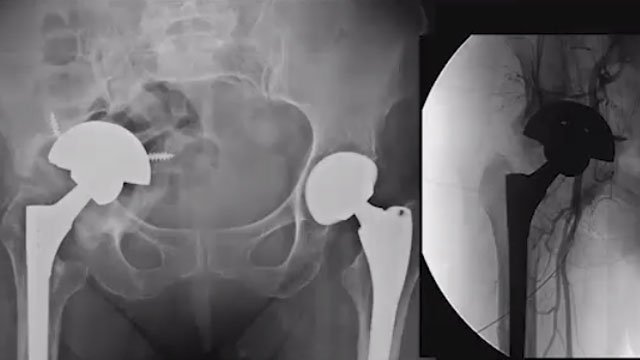

Revision hip replacement surgery is performed when a previously implanted hip joint requires replacement or repair. This procedure may be recommended for individuals experiencing ongoing pain, joint instability, or other issues related to their original hip replacement. Revision surgery can address complications and improve joint function, although it is often more complex than the initial procedure.

Revision hip replacement involves removing and replacing some or all components of a previously implanted hip joint. It may address issues such as implant wear, infection, or mechanical failure. This surgery requires careful planning and expertise to achieve optimal outcomes.

- Procedure Steps: The surgeon removes the old implant, addresses any damage or infection, and places the new implant. Bone grafts may be used to repair weakened areas.